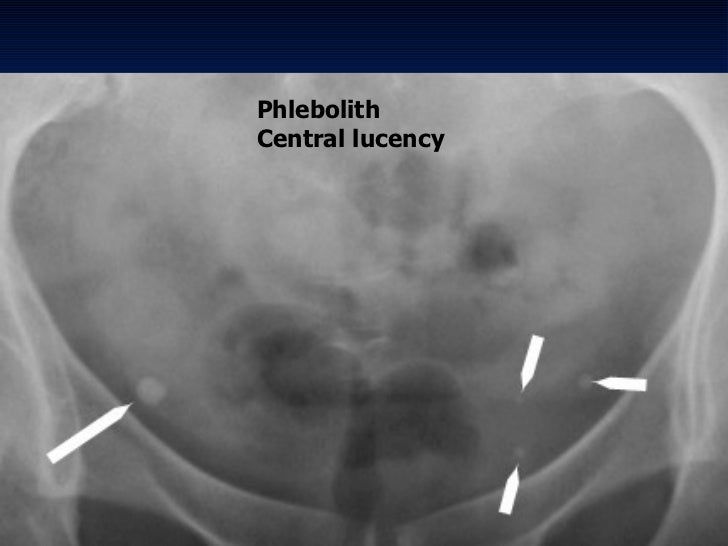

Small Calcifications In The Pelvis On XRay Radiology In Plain English What Are Vascular Phleboliths These are very common in the veins of the lower part of the. Phleboliths are tiny calcifications (masses of calcium) located within a vein. They are sometimes called “vein stones.” the phlebolith starts as a blood clot and hardens over time with. Generally, researchers don’t fully understand what causes phleboliths. A phlebolith is a small local, usually rounded, calcification within. What Are Vascular Phleboliths.